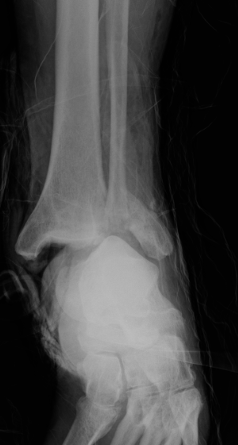

ORIF

Aigner et al Foot Ankle Int 2017

- 237 ankle fractures > 65 years treated with ORIF

- complication rate 29%

- most common wound healing and wound infection

Hindfoot nail

- systematic review of hindfoot nail for fragility fractures

- union 90 - 100%

- allowed early rehabilitation and restoration of function

- RCT of ORIF v hindfoot nail for fragility fractures in 87 patients

- lower rate of complications with nail (8% v 33%)

- shorter hospital stay with nail

- no difference in outcome